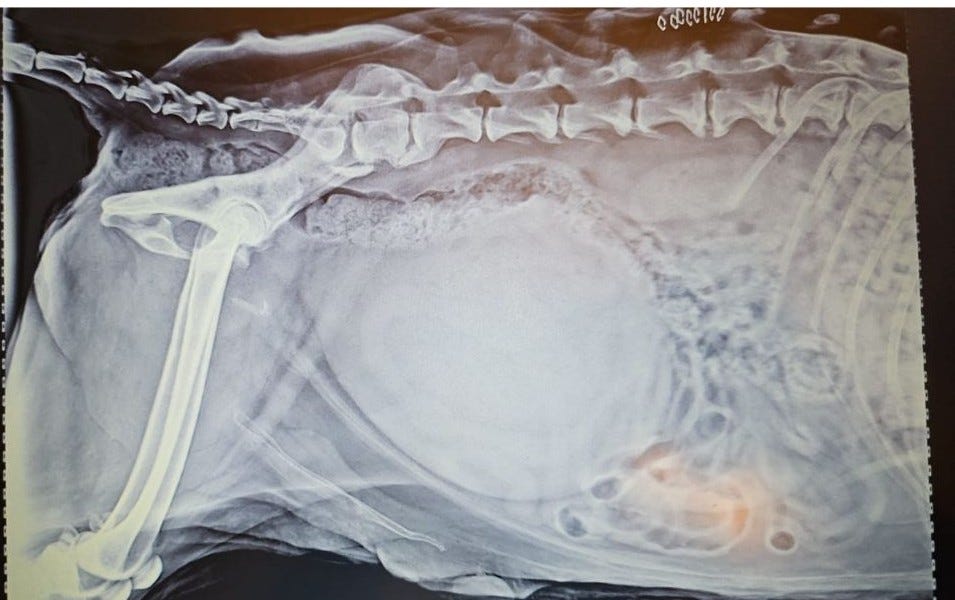

Jude's initial X-ray which came from the vet who saw Jude at the beginning revealed a bullet that the previous vet had removed. However, it was not situated in a way that would have caused Jude's paralysis.

Unfortunately, removing the bullet did not resolve any of the issues. Jude’s new x-rays showed a fused spine, an enlarged bladder, and a fractured hip.